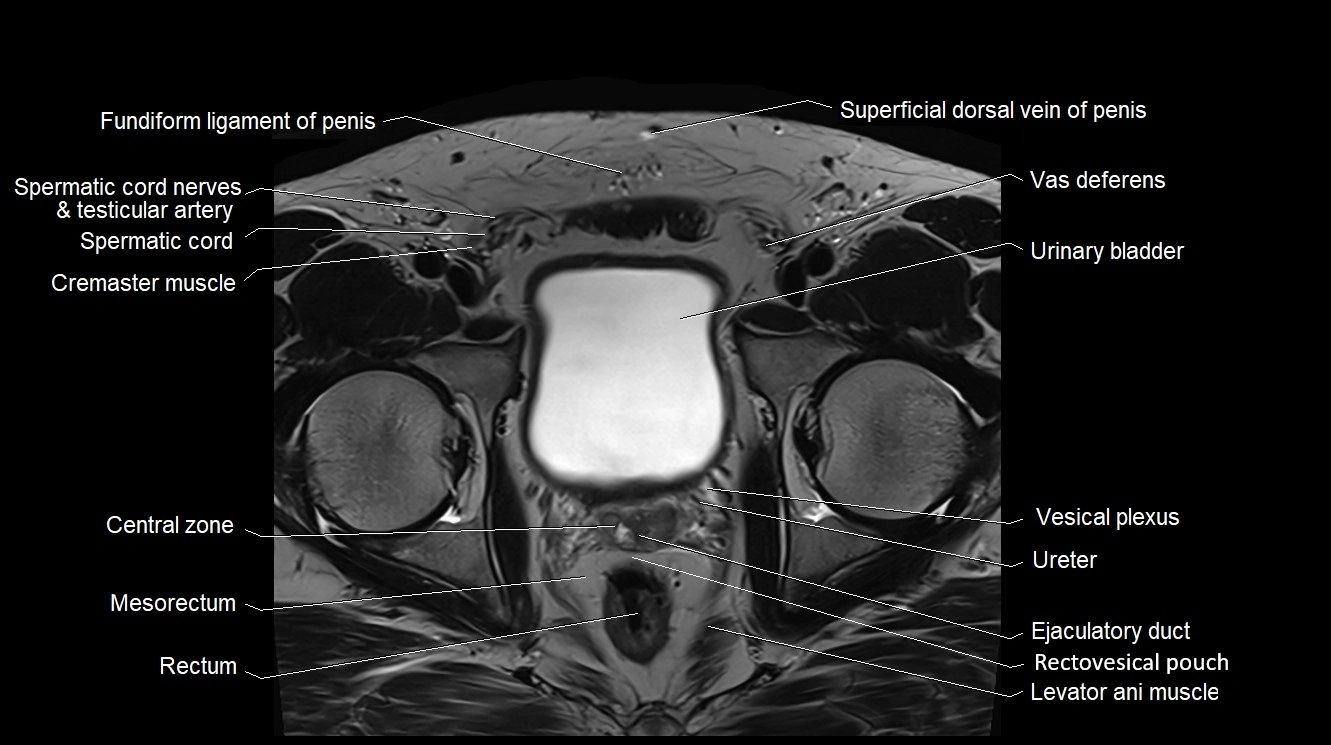

- Spermatic cord

- Spermatic cord nerves

- Cremaster muscle

- Superficial dorsal vein of penis

- Vas deferens

- Urinary bladder

- Central zone of prostate

- Mesorectum

- Rectum

- Ejaculatory duct

- Rectovesical pouch

- Levator ani muscle

- Pampiniform plexus